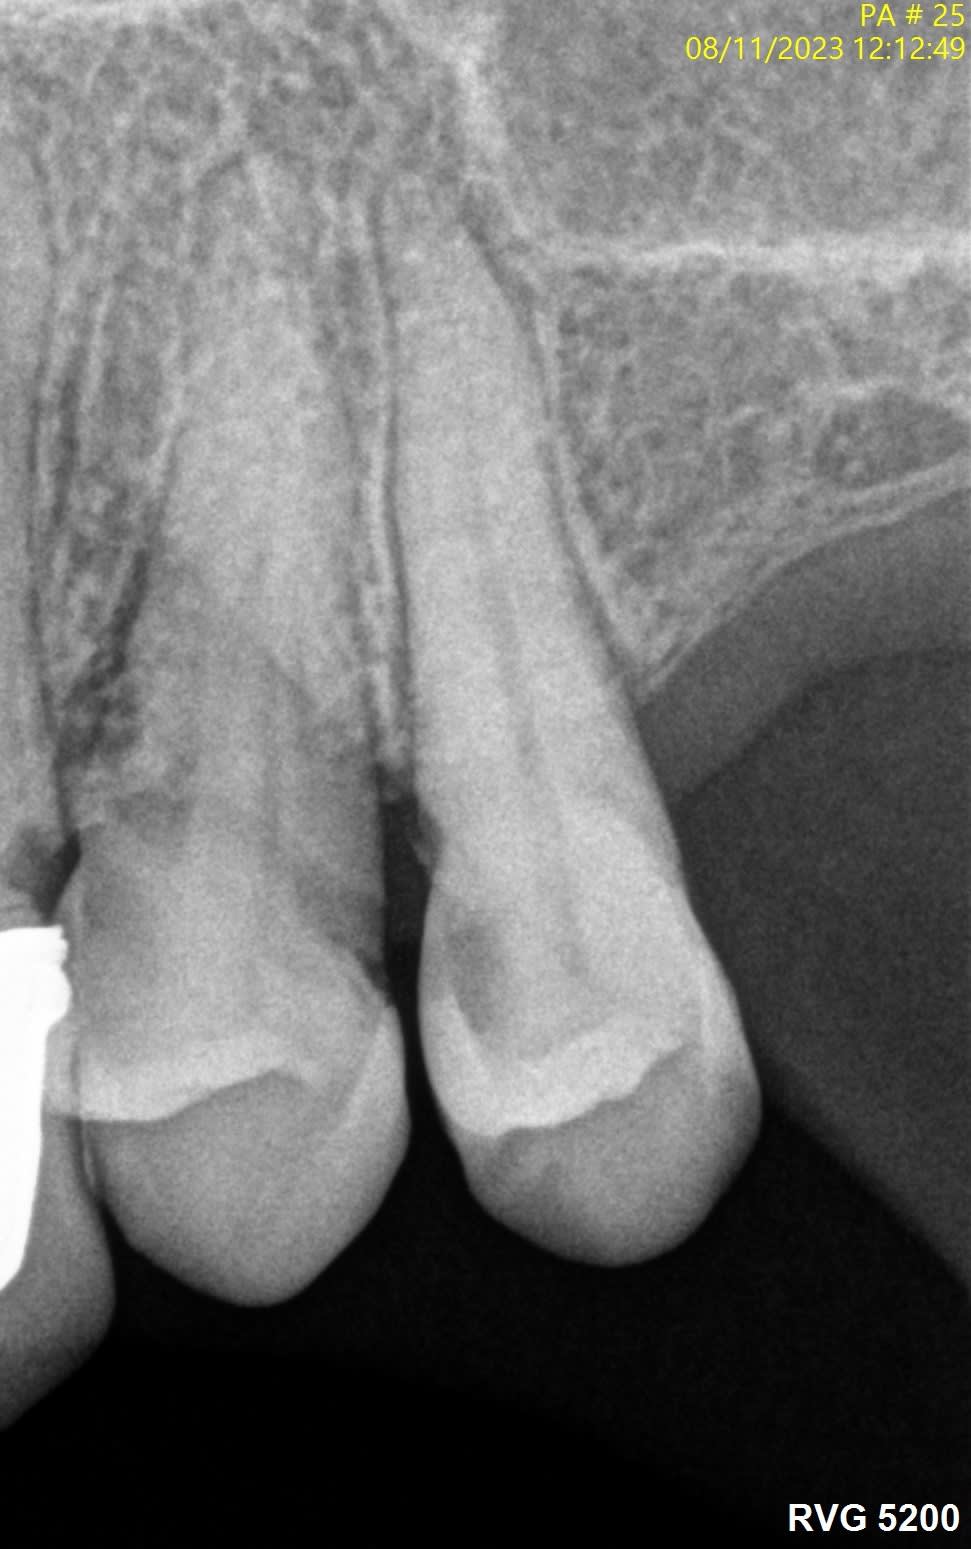

Voici quelques radio pour illustrer...

J’ai l’impression que sur les radios que tu montres il y a des fractures verticales.

La 24 et la 25, t'aurais carrément dû les virer...

> La 24 et la 25, t'aurais carrément dû les virer...

Du tout, c'est joli la zircone, et c'est gratuit.

Sur des endo avec une pulpe saine comme les 24 25, en t'arrêtant à 5 mm, tu auras le même taux de réussite qu'à 0.

J’élargis très progressivement pour limiter les contraintes sur les racines et les fissurations notamment dans les derniers mm apicaux. Je passe un wave one gold 20 avant le r25, une piste peut être.